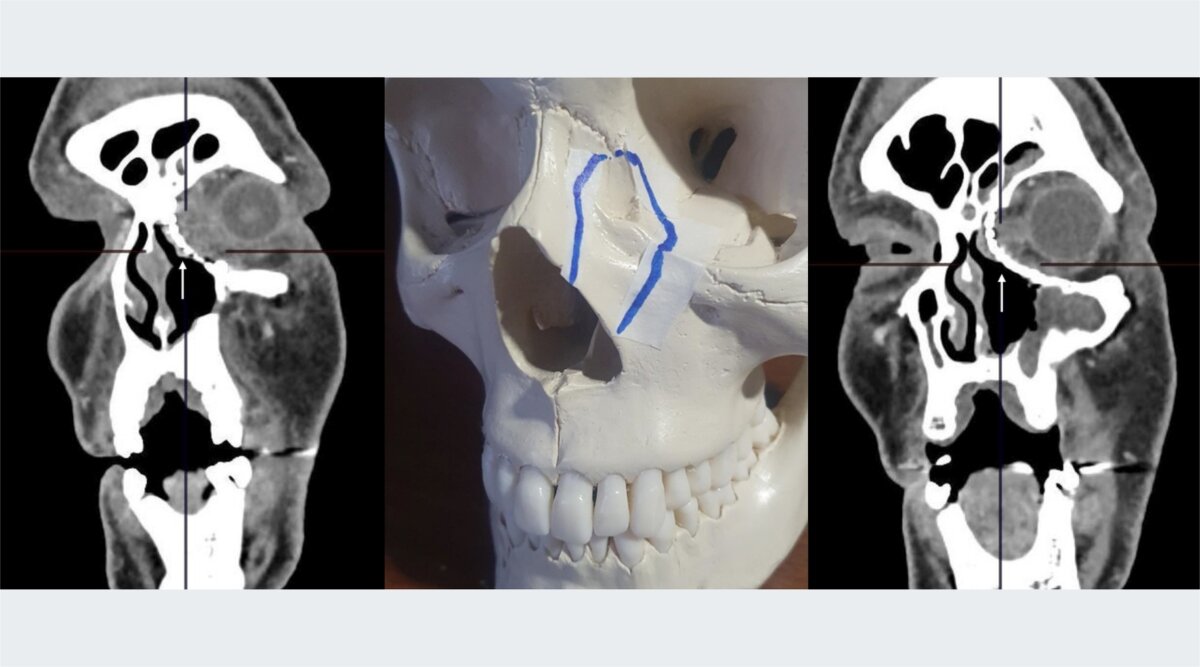

Фото: Онкоцентр №1 ГКБ им. С.С. Юдина

«Опухоль была удалена в блоке с кожей и мягкими тканями внутреннего угла век левого глаза, фрагментами носовой кости, внутренней стенки глазницы и передней стенки верхне-челюстной пазухи вместе со слезным мешком и слезным каналом. Целостность глазного яблока и глазодвигательного аппарата полностью сохранена. Покровные ткани лица восполнены кожно-апоневротическим лоскутом со лба», – рассказал Сергей Кравцов.

Для сохранения внешнего облика пациента и его бинокулярного зрения было выполнено восстановление опорных структур лицевого скелета (носовой кости, глазницы и верхнечелюстной пазухи) путем эндопротезирования титановой конструкцией. Пациент чувствует себя хорошо и доволен результатом операции, в том числе эстетическим.